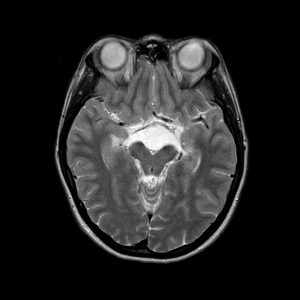

Lao màng não

Lượt xem: 403» 19-06-2020 -